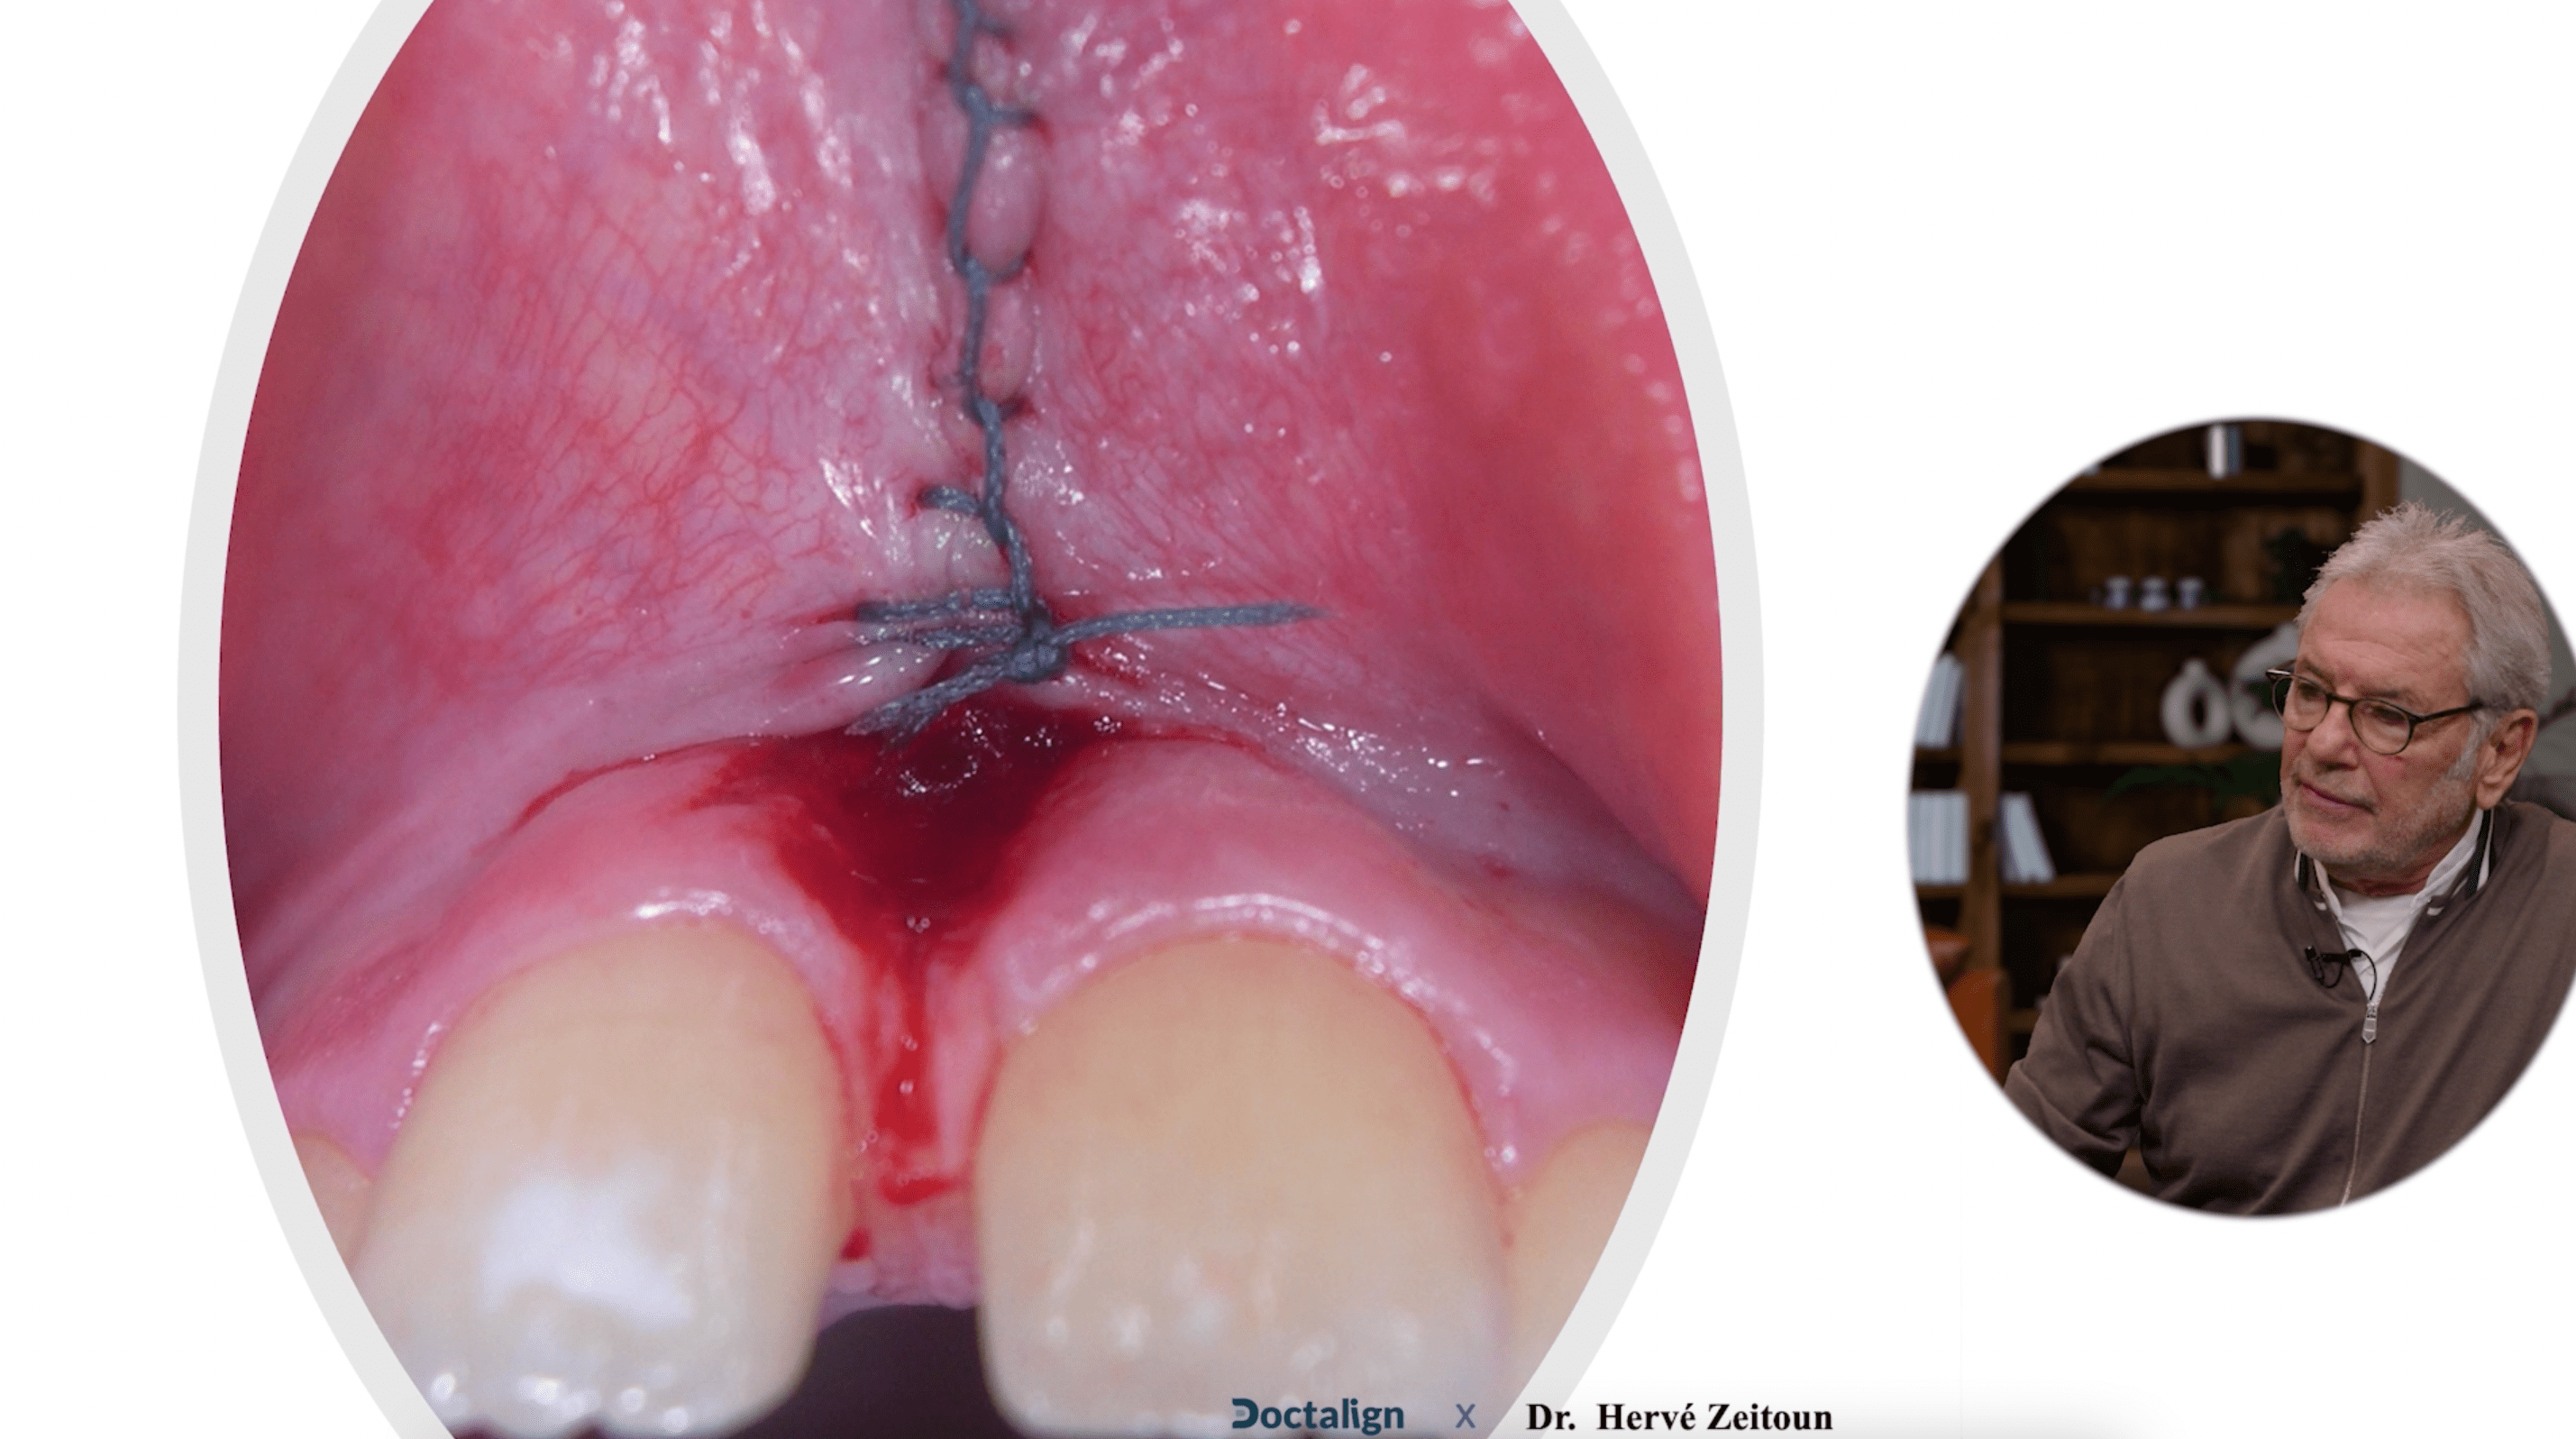

Techniques chirurgicales

Ce chapitre de la formation détaille pas à pas les techniques chirurgicales spécifiques du Dr. Zeitoun pour la frenectomie, offrant des méthodes précises et innovantes qui optimisent l'efficacité du processus, permettant ainsi de gagner un temps précieux lors de l'intervention.